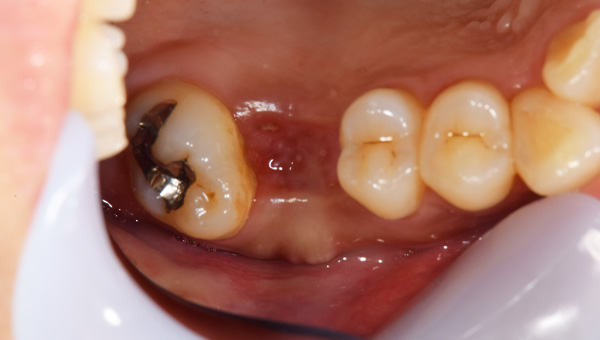

初診時の口腔内

説明:

初診時の口腔内です。かぶせ物があり、一見虫歯とはわからないです。